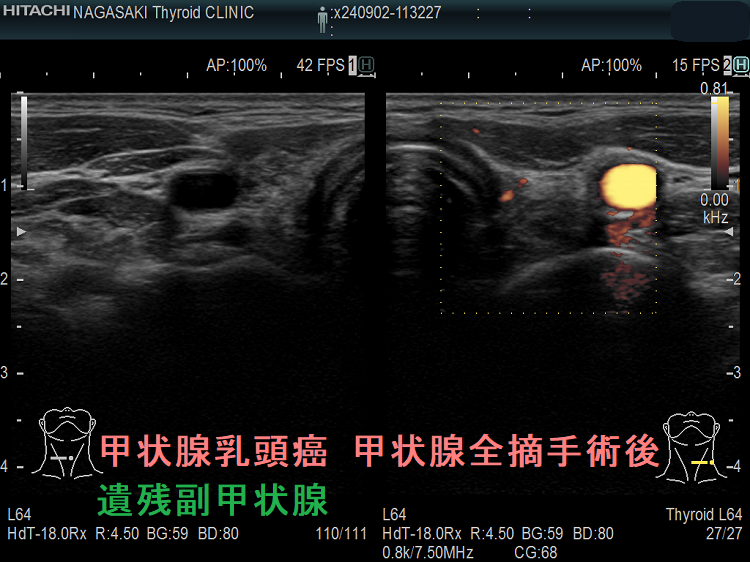

- 甲状腺摘術後、TSH 抑制療法;バセドウ病/甲状腺腫瘍で甲状腺切除と同時に副甲状腺も取ってしまった場合、取らずに温存した場合でも副甲状腺への血管を傷つけた場合

- 頭頚部癌、サルコイドーシスで頚部手術後・放射線照射後の副甲状腺損傷・副甲状腺切除

- 甲状腺癌、頭頚部癌の副甲状腺浸潤

- 甲状腺全摘術時、副甲状腺も1-4腺を同時切除、あるいは切除しなくても栄養血管を損傷

- 甲状腺亜全摘術時、副甲状腺を数腺温存したつもりが、栄養血管を損傷

- 術後副甲状腺機能低下症による低カルシウム血症;術直後のみならず、10年~30年以上して著明な低カルシウム血症で発症する事もある(日腎会誌 2012;54(1):40-47.)(J Clin Diagn Res. 2017 Feb; 11(2): OD07–OD09.)。